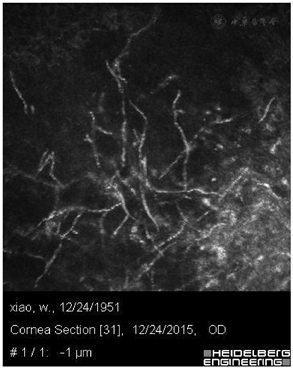

首诊医师根据裂隙灯下眼部查体,考虑真菌性角膜炎,反复询问患者病史,最终获知:发病前患者曾用自制的桑叶水反复洗眼。遂给予HRT-3辅助检查,示:右眼角膜溃疡灶见细长菌丝(图1,图2,图3)。临床诊断:右眼真菌性角膜炎。

HRT-3示:右眼角膜溃疡灶见细长菌丝,炎性细胞。